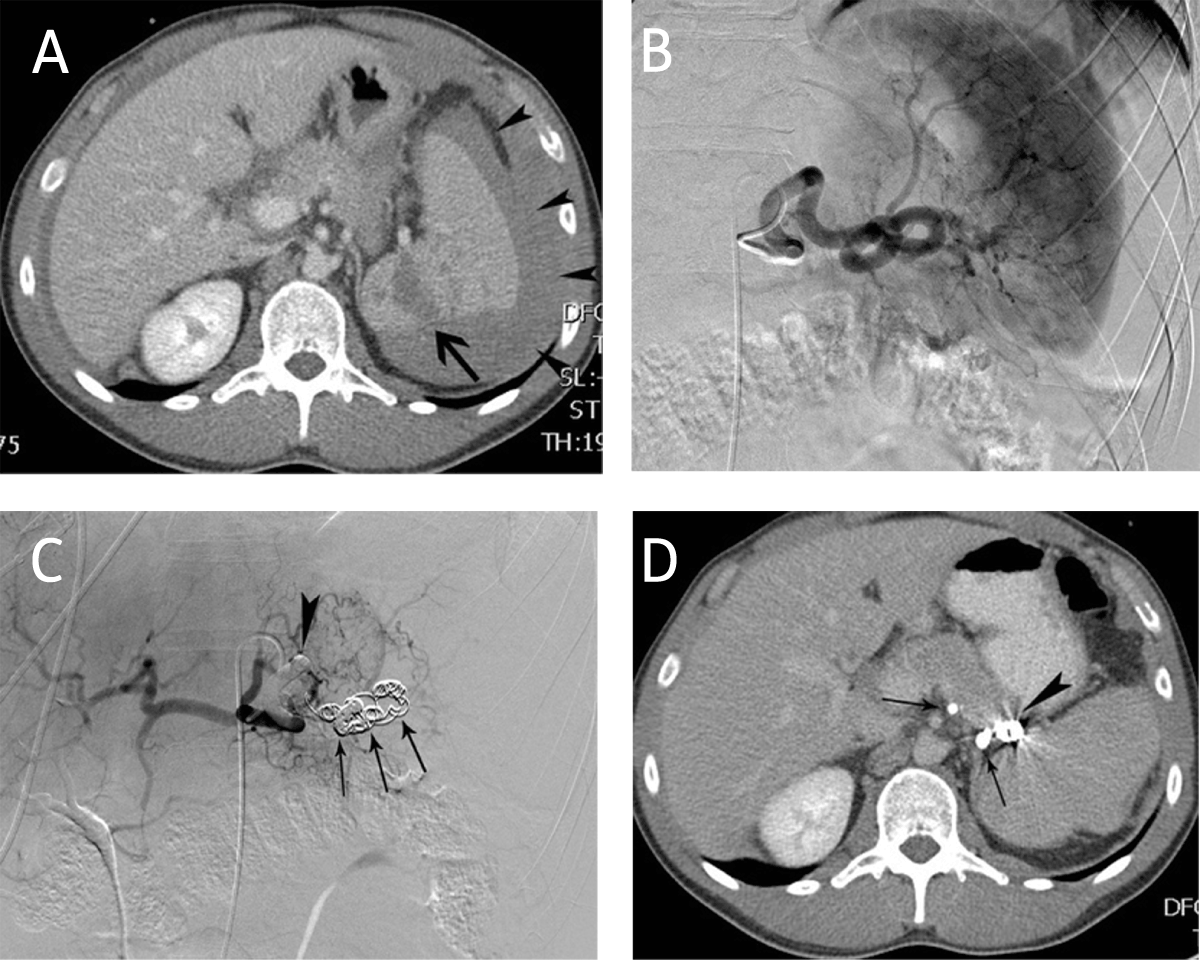

Figure 2

Main splenic artery embolization for trauma. (A) CT-scan in a 27-year-old man after a traffic accident revealed splenic laceration (arrow) and a perisplenic hematoma (arrowheads). The volume of the spleen was 270 ml. (B) Corresponding selective splenic angiography did not reveal contrast extravasation. (C) Main splenic artery embolization was performed with coils (arrows) and glue (arrowhead). (D) Follow-up CT-scan 8 months later demonstrated the glue (arrows) and coils (arrowhead) in the splenic artery. The total splenic volume was 290 ml.